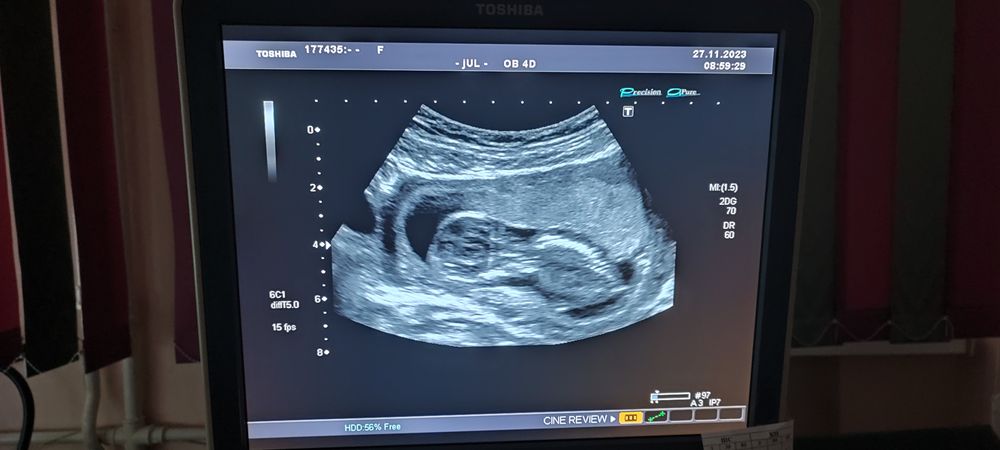

История успешного зачатияДевчули, это длиннейший мегапост, и в нем будет ооочень мноого того, что кажется необычным на первый взгляд. Возможно кому-то он поможет взглянуть на некоторые процессы иначе. Я хотела написать его именно после того, как придет результат анализа на определение пола нашего малыша. Позавчера мы его получили:

Сын - это наша с мужем сбывшаяся мечта. Я не буду раздумывать о причинах, по которым такая мечта в нашей жизни появилась, суть именно в том, что сегодня она сбылась. По крайней мере сейчас я точно знаю, что у моего мужа присутствуют спермики мужского пола)))